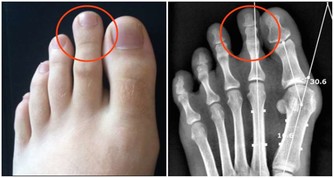

9. 腳和小腿疼痛

小腿上的深靜脈血栓,會造成嚴重的疼痛,使人步行困難並且坐著也會疼。不僅如此,腳部疼痛也是其後果之一,由於血栓妨礙血液流向足部,導致足部缺氧,造成嚴重不適。